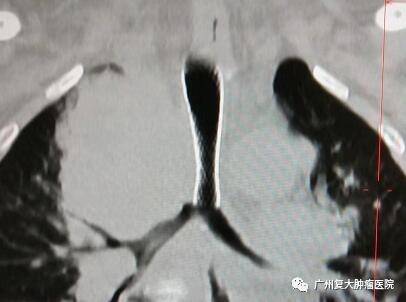

同樣,食管癌手術、放療后復發(fā)等多種因素導致吻合口狹窄是常見的問題,患者不能進食,生活質量下降?;颊邚埾壬惨蚝韲挡贿m,吞咽困難,在當?shù)蒯t(yī)院進行檢查后被確診為“食管癌”,并接受了食管癌根治術,術后出現(xiàn)吻合口瘺及吻合口狹窄,實行3次食管擴張術。為抑制腫瘤的增長,他開始進行放化療治療和藥物治療,但不僅化療都讓張先生痛苦萬分,還出現(xiàn)吞咽困難,胸悶心慌,呼吸困難,左上肢肌力減退、疼痛、麻木等癥狀。

為進一步診療,張先生來到我院就診。張先生因嚴重氣管狹窄引起呼吸困難,時間急迫,在與家屬多次溝通并取得同意后,在DSA+CT影像技術引導下,牛立志院長為其實行緊急氣管支架植入+腫瘤射頻消融術。術后第二天,張先生下床活動自如,原來胸悶、心慌、呼吸困難等癥狀全都消失了。他激動地找到牛院長說:“牛院長,太感謝你啦,我現(xiàn)在感覺呼吸順暢很多了。”

牛立志院長表示,對于食管癌或其他病因引起氣道狹窄的患者,氣管支架植入治療目的就是可使不通的管道變得通暢,迅速緩解腔道狹窄的癥狀,改善患者呼吸狀態(tài),避免窒息發(fā)生,提高患者生活質量并為后續(xù)治療奠定了基礎。